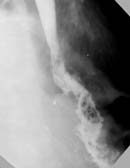

В последующем медиастинальный затек сообщался со свободной плевральной полостью. В этом случае рентгенологическая картина трактовалась уже как плевральный затек (Рис. 3). Контрастное вещество растекалось по медиастинальной и диафрагмальной плевре, преимущественно в задних отделах плевральной полости. Следует отметить, что рентгенодиагностика явной несостоятельности швов анастомоза не вызывала затруднений.

Рис. 3. Медиастоплевральный затек